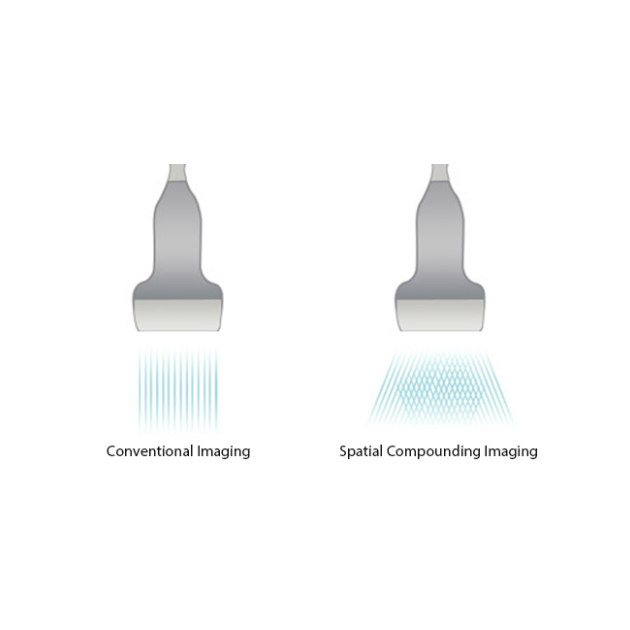

iBeamTM

Permits use of multiple scanned angles to form a single image, resulting in enhanced contrast resolution and improved visualization.